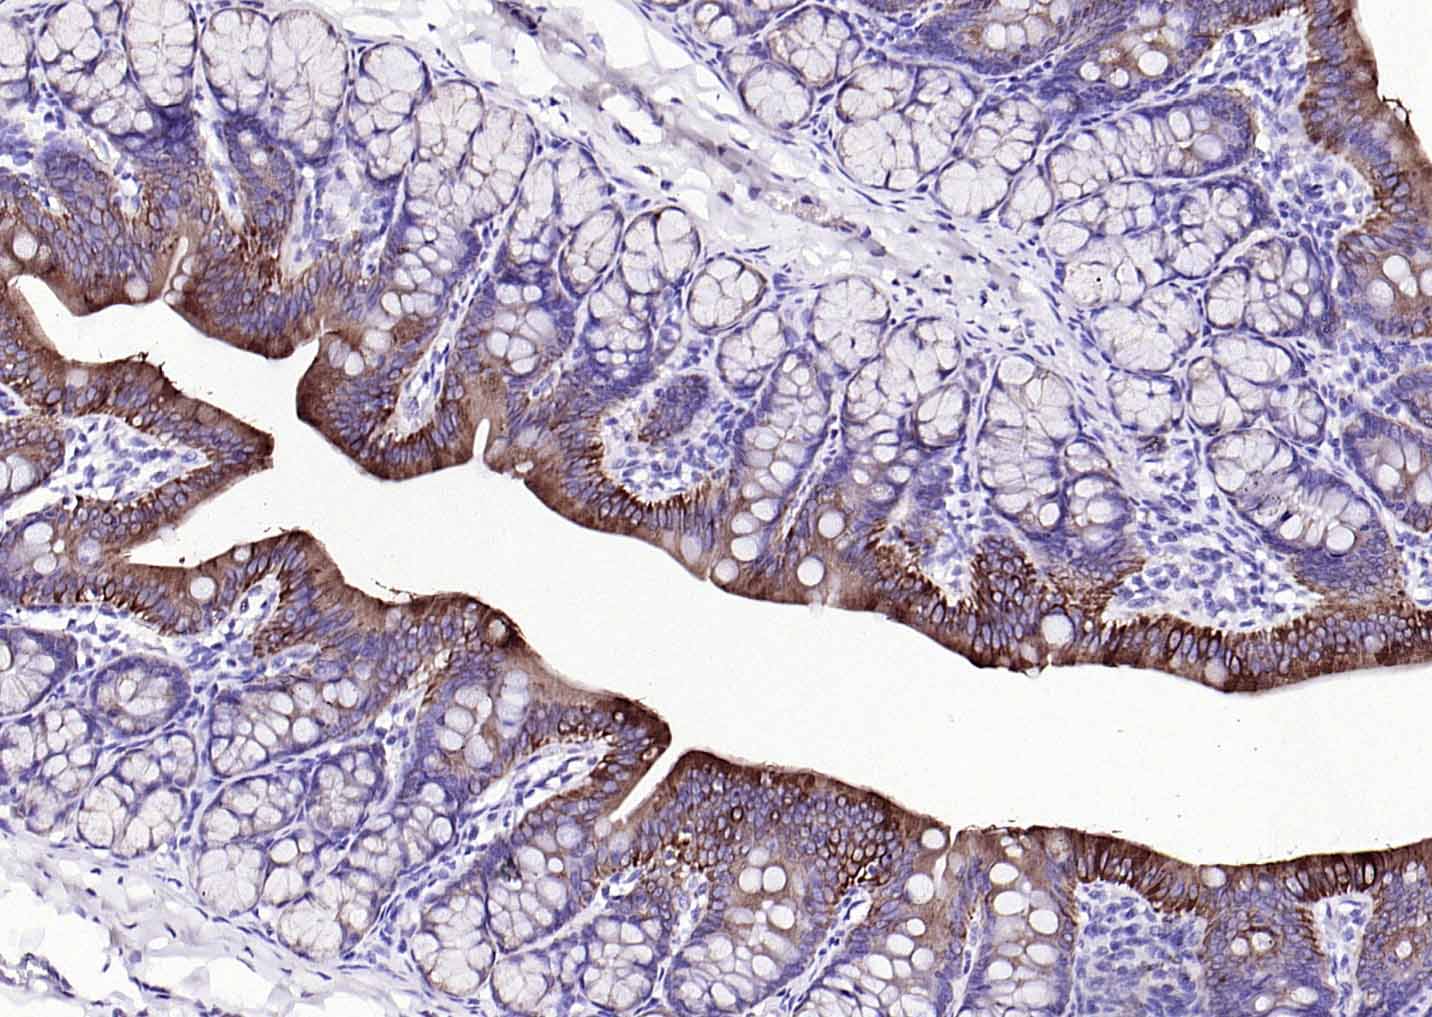

Vimentin is a developmentally regulated intermediate filament protein (IFP) found in cells of mesenchymal origin. It is believed to be involved with the intracellular transport of proteins between the nucleus and plasma membrane. Unlike other IFP proteins, vimentin is expressed, along with desmin, during the early stages of cellular development. During the development process, vimentin is exchanged for new, tissue-specific IFPs. Vimentin has been implicated to be involved in the rate of steroid synthesis via its role as a storage network for steroidogenic cholesterol containing lipid droplets. Vimentin phosphorylation by a protein kinase causes the breakdown of intermediate filaments and activation of an ATP and myosin light chain dependent contractile event. This results in cytoskeletal changes that facilitate the interaction of the lipid droplets within mitochondria, and subsequent transport of cholesterol to the organelles leading to an increase in steroid synthesis.

| IHC-P | Human, Mouse, Rat | 1:100-500 | |